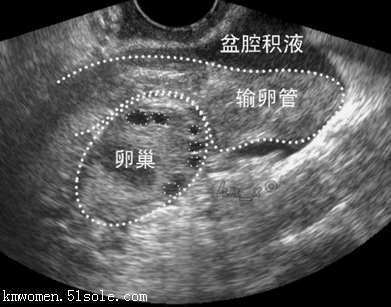

有的女性可能会感觉肚子胀,在感觉肚子胀的时候她们会去医院做检查,检查结果发现有腹腔积液多,她们不知道导致这个问题出现的原因,那么,女性腹腔积液产生的原因是什么?来看答案。

上面就是女性腹腔积液产生的原因介绍,如果发现自己有被这样的问题困扰,建议要进一步做检查,通过检查的结果来看需要怎么处理这样的异常情况,这样才能够让自己的相关病症能够及时得到治疗。